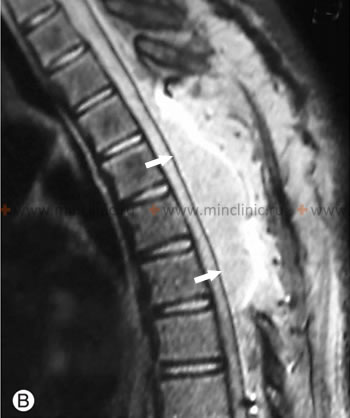

კისრის მალთაშუა დისკების დაშლის (ექსტრუზიები, თიაქრები) მალთაშუა სახსრების თანმხლები ოსტეოართროზითა და უკანა და ყვითელი იოგის ჰიპერტროფიით (კისრის სპონდილოზი) იწვევს ქრონიკულ მიელოპათიას ზურგის ტვინის კისრის დონეზე ხანდაზმულ პაციენტებში.

ხერხემლის სვეტის კისრის მაგნიტურ-რეზონანსულ ტომოგრაფიაზე C5-C6 დისკის თიაქარი ზეწოლას ახდენს ზურგის ტვინზე კისრის დონეზე და იწვევს კომპრესირებად მიელოპათიას.